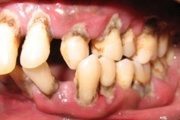

Agressiivse parodontiidi kahjustused rasedal naispatsiendil